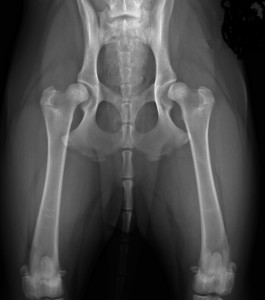

Voici des hanches d’un chien dysplasique. L’ostéoarthrose a envahit les hanches. On voit facilement que la tête fémorale est déformée par du remodelage osseux de l’articulation qui tente en vain de se stabiliser pour se protéger.